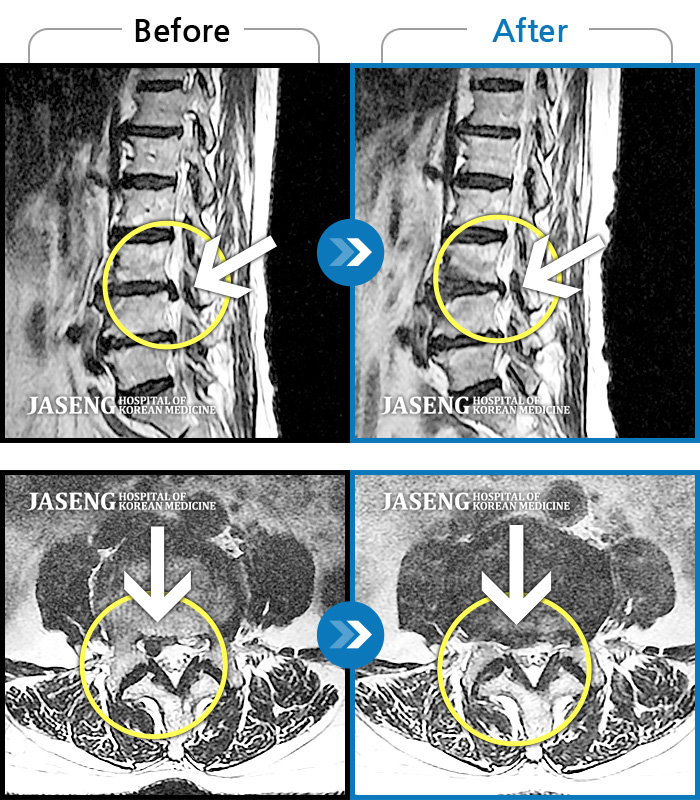

MRI 치료사례

허리디스크

일산 · 배영현 교육수련부장

허리, 좌측 골반부터 좌측 다리로 통증 및 저림이 지속되고 좌측 다리의 감각이 둔함

촬영시기

2024.09.30 ~ 2025.11.25

2025.12.05